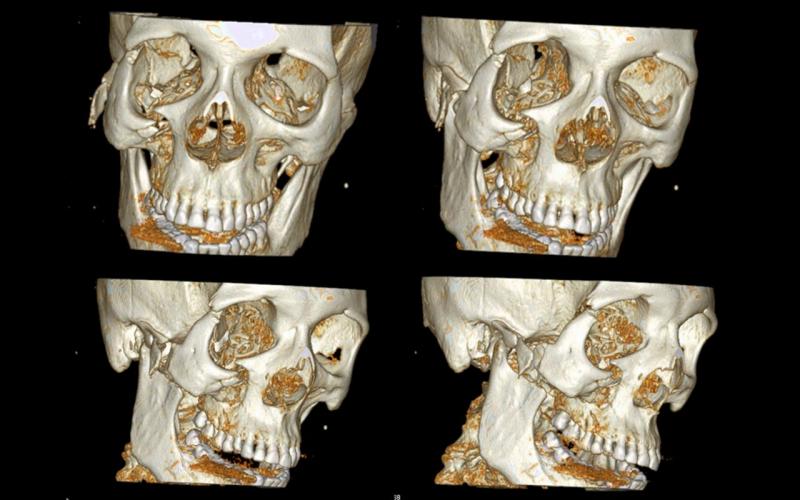

Diagnosis and treatment of dysgnathia, and orthognathic reconstructive surgery, genioplasty, maxillo-mandibular advancement/set-back, and surgical correction of facial asymmetry (See Images Below)